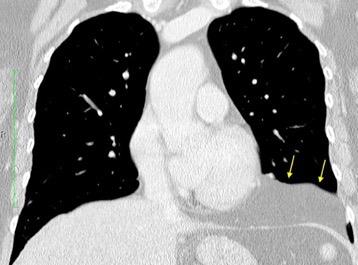

37. ESPLENOSIS TORÁCICA

Autotrasplante de tejido esplénico al tórax tras trauma. (T. Penetrante más frecuente que cerrado)

Causas:

1. Trauma 2.Esplenectomía

3. Diseminación hematógena

4. ¿Hipoxia?

T1: Hipointenso

T2: Hiperintenso. Puede ser hipointenso. (Hierro)

Esplenectomía previa

Ferrer TM et al. Thoracic splenosis: History is the key. Respiratory Medicine Case Reports. 2017